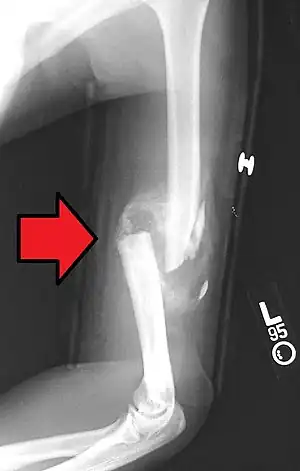

A fibrocartilage callus is a temporary formation of fibroblasts and chondroblasts which forms at the area of a bone fracture as the bone attempts to heal itself. The cells eventually dissipate and become dormant, lying in the resulting extracellular matrix that is the new bone. The callus is the first sign of union visible on x-rays, usually 3 weeks after the fracture. Callus formation is slower in adults than in children, and in cortical bones than in cancellous bones.[1]